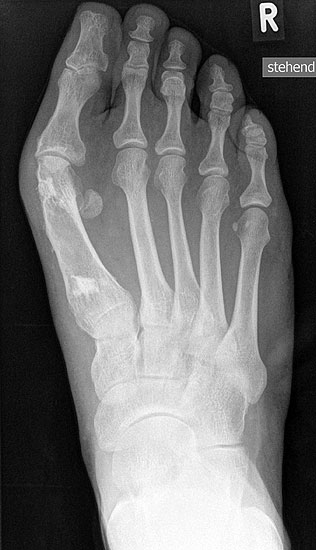

Die Röntgenaufnahmen (Abbildung 1) zeigen den Fuß einer 34 jährigen Patientin nach Exostosenabtragung. Der erhöhte intermetatarsale Winkel wurde durch eine alleinige Abtragung der Exostose nicht reduziert. Als weiterer Risikofaktor für ein Rezidiv liegt ein pathologischer Gelenkwinkel vor. Der intermetatarsale Winkel von 18 Grad kann durch eine basisnahe Osteotomie gut korrigiert werden. Da durch die gleichzeitige distale Korrektur des Gelenkflächenwinkels mithilfe einer Reverden-Green Osteotomie ein Längenverlust von ca. 2-4 mm einhergeht, bot sich als proximales Korrekturverfahren die basisnahe Open-wedge Osteotomie an, um bezüglich der Länge des Metatarsale I neutral zu bleiben (Abbildung 2). Die Kombination zweier verkürzender Verfahren (z.B. Lapidus und Reverden-Green) würden zu einem sehr kurzen ersten Strahl führen, mit dem Risiko einer Transfermetatarsalgie. Übersteigt die Verkürzung des Metatarsale I 2 mm, steigt das Risiko für die Entwicklung einer Transfermetatarsalgie deutlich an 8. Die durchgeführte Revision zeigt eine gute Stellung des 1. Strahls bei zentriert stehendem Gelenk.